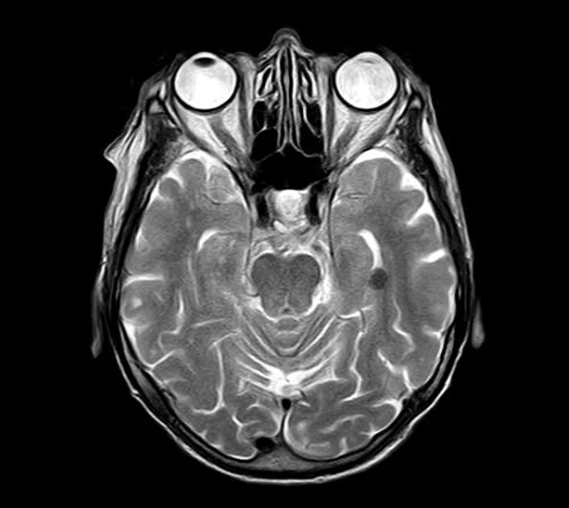

의학 기술의 발전으로 질병의 조기 진단과 정밀한 치료가 가능해졌습니다. 그중에서도 MRI검사는 인체의 연부조직을 고해상도로 촬영할 수 있는 고급 영상진단 장비로, 뇌, 척추, 관절, 내부 장기 등 다양한 분야에서 활용됩니다.

MRI(Magnetic Resonance Imaging)는 강한 자기장과 라디오파를 이용하여 인체 내부 구조를 촬영하는 영상검사입니다. X-ray나 CT와는 달리 방사선을 사용하지 않아 비교적 안전하며, 근육, 인대, 뇌, 척수와 같은 연부조직을 정밀하게 확인할 수 있습니다.

- 뇌 및 신경계 질환: 뇌졸중, 뇌종양, 치매, 간질 등